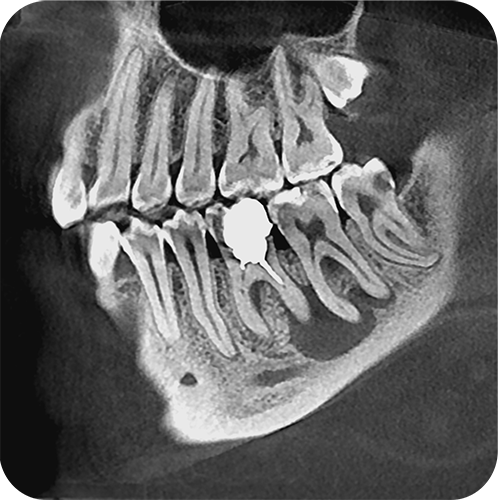

На выставке «Дентал Экспо Красноярск» успешно прошло заседание главных врачей во главе с Садовским Владимиром Викторовичем, Вице-президентом Общества Врачей России, Почетным Президентом СтАР, Директором Национального института исследований и адаптации маркетинговых стратегий (НИИАМС). Помимо насущных вопросов, руководители организаций региона обсудили преимущества и возможности использования стоматологического томографа Genoray Papaya 3D.

- Плоскопанельный детектор имеет самую высокую в классе разрешающую способность